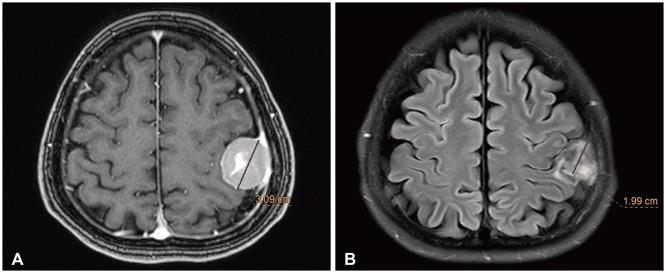

This preliminary study evaluates the safety and efficacy of CyberKnife radiosurgery (CKRS) for large-volume meningiomas (≥10 cm³), where surgical options may be limited due to tumor location or patient health conditions.

We retrospectively analyzed 18 patients with meningiomas treated with CKRS at Gyeongsang National University Hospital between 2010 and 2020. Tumor control and survival rates were evaluated, with follow-up imaging performed regularly.

CKRS achieved a 5-year overall survival rate of 92.3% and a 5-year tumor control rate of 93.8%. Symptomatic peritumoral edema occurred in 61.1% of patients, with 16.7% requiring surgical intervention.